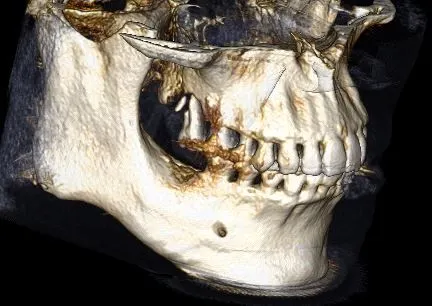

Case 4